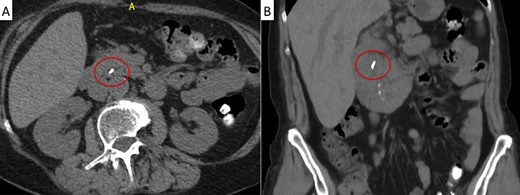

A 71-year-old woman with a history of LC for acute cholecystitis 6 years earlier was admitted with right upper quadrant abdominal pain, jaundice and fever. On admission, her vital signs were body temperature 38.2°C, pulse rate 96/min, respiration rate 21/min, blood pressure 100/60 mmHg and SpO2 98%. Her laboratory tests showed leukocytosis (19.200/ml), an erythrocyte sedimentation rate of 25 mm/h, C-reactive protein of 26 mg/l and altered liver function tests with cholestatic pattern: total bilirubin 4.95 mg/dl (normal up to 1.2), direct bilirubin 4.18 mg/dl, alkaline phosphatase 1083 IU/l (normal up to 150), gamma-glutamyl transferase 169 IU/l (normal up to 45), aspartate transaminase 281 IU/l (normal up to 40) and alanine transaminase 330 IU/l (normal up to 41). Serum amylase and lipase were normal. Abdominal ultrasound showed biliary tract dilatation but not obstructive cause, with a maximum diameter of the CBD of 17.6 mm. A subsequent magnetic resonance cholangiopancreatography (MRCP) found a filling defect in the distal CBD (Fig. 1). ERCP extraction was attempted, but it was impossible to progress the catheter due to an irregular distal bile duct stenosis. An abdominal computed tomography (CT) scan was therefore performed and showed a foreign body with radiopaque characteristics in the distal CBD consistent with a metallic clip (Fig. 2). Given that the object could not be removed by ERCP due to technical difficulties in biliary cannulation, laparoscopic bile duct exploration was decided.

Magnetic resonance cholangiopancreatography (MRCP) showing a filling defect in the distal bile duct (red circle).